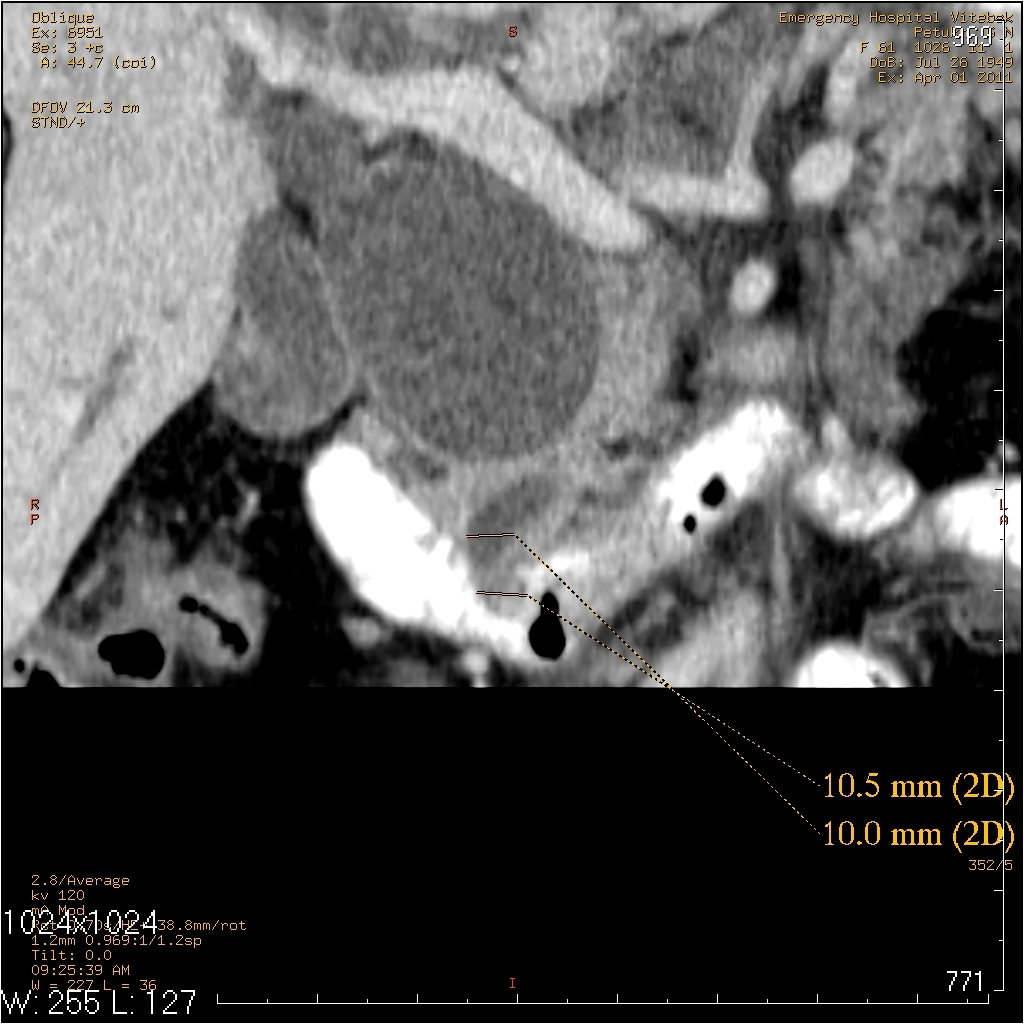

На МСКТ: Киста холедоха (грушевидной формы ~95х50мм). ЖКБ: холецистит, холедохолитиаз (в области БДС дефект наполнения просвета 12пк, расширение вирсунгова протока до 10мм). Билиарная гипертензия. Отёчный панкреатит, парапанкреатит.

На операции: Киста холедоха (терминальный отдел холедоха 2мм). ЖКБ: хр.холецистит, холедохолитиаз (конкременты до 4мм). Стеноз папилы 3ст. (блокада вирсунгова протока, общий желчный и панкреатический протоки впадают в двенадцатиперстную кишку по отдельности). Острый панкреатит, парапанкреатит.